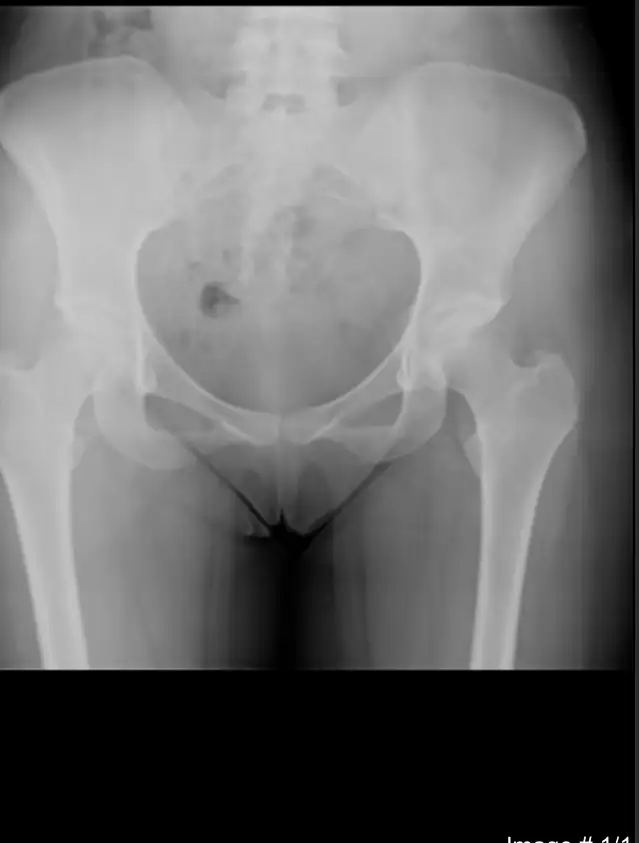

C c12n8vra Yeni Üye Kayıtlı Üye 16 Ağustos 2021 6 0 1 25 21 Eylül 2021 Konu Sahibi Konu Sahibi c12n8vra #1 4. Haftada ve 8.haftada idrarda gebelik testi yaptım negatif cıktı . Bugün de röntgen çekildim baska bir sıkıntı icin bir karartı vardı . Çikolata kistim mi yoksa gebelik mi emin değilim . Röntgende gebelik görünür mü ? Eklentiler 7CBD5960-3F6D-4E12-807E-C762F53B9B41.webp 6,1 KB · Görüntüleme: 877

4. Haftada ve 8.haftada idrarda gebelik testi yaptım negatif cıktı . Bugün de röntgen çekildim baska bir sıkıntı icin bir karartı vardı . Çikolata kistim mi yoksa gebelik mi emin değilim . Röntgende gebelik görünür mü ?